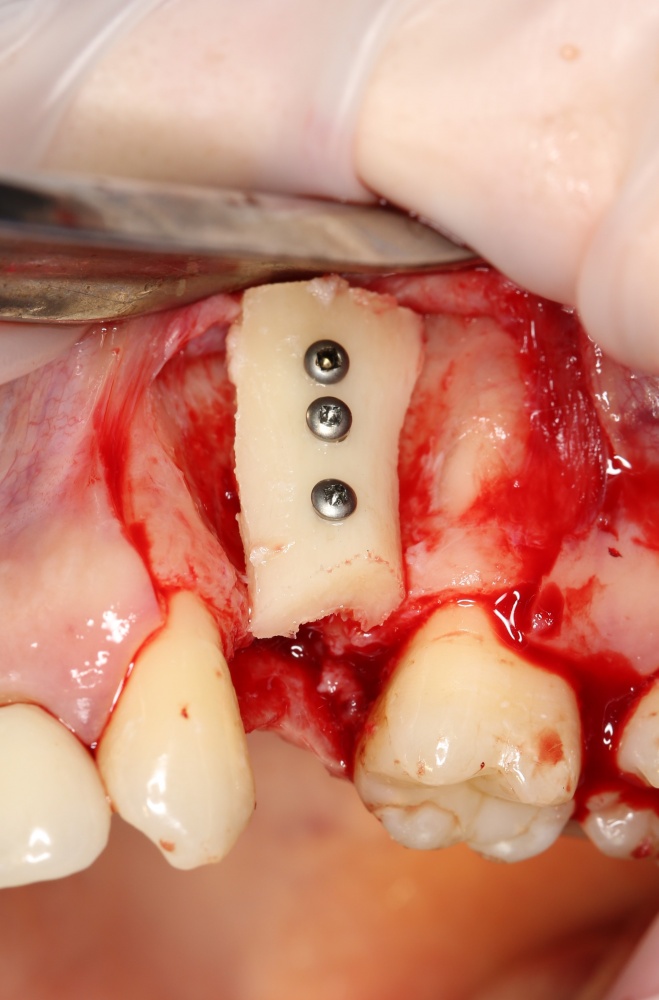

Простой. Надежный. Дешевый. Способ остеопластики.